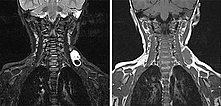

In der koronaren MRT (linkes Bild: T2-Wichtung, rechtes Bild: T1-Wichtung nativ) ist die venöse Malformation sehr gut abgrenzbar. In der T2-Wichtung ist sie stark hyperintens, in der nativen T1-Wichtung isointens zur Muskulatur. Die Signalgebung ist klassisch für den Charakter einer Slow-flow-Läsion.

In der koronaren MRT (linkes Bild: T2-Wichtung, rechtes Bild: T1-Wichtung nativ) etwas weiter dorsal, ist sehr gut ein größerer Thrombus innerhalb der venösen Malformation abgrenzbar. In der T2-Wichtung ist dieser hypointens im Vergleich zur stark hyperintensen VM. In der nativen T1-Wichtung ist er ganz gering hyperintenser als die umgebende hypointense VM.